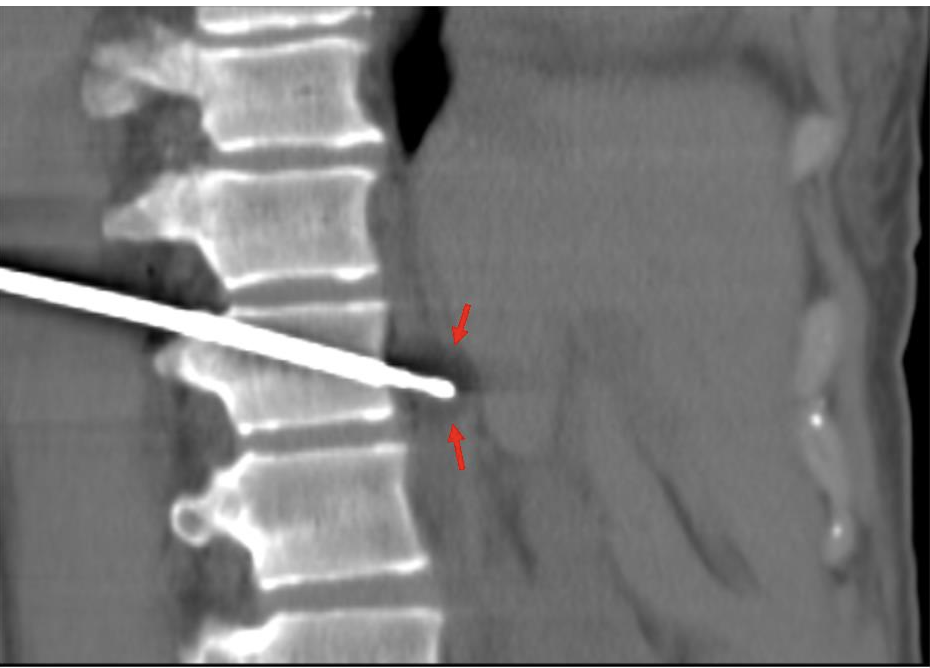

The patient was positioned prone oblique on the CT table (Figure 2). The procedure was performed under general anesthesia given the prone positioning, required precision for needle placement, and anticipated length of cryoablation. Under CT guidance, an 11-gauge bone access needle was advanced via a left transpedicular approach across the T12 vertebral body. Coaxial technique through this access was used to obtain both fine needle aspiration (FNA) and core biopsy samples (Figures 3-4). Immediate pathology assessment of the FNA samples confirmed metastatic adenocarcinoma. A single Endocare 17R cryoablation probe (Varian) was advanced through the 11-gauge access needle into the center of the nodal metastasis. Cryoablation was performed for 3 freeze-thaw cycles with intermittent CT monitoring to ensure adequate coverage of the lymph node and to minimize injury to the adjacent normal structures (Figures 5-6). All needles were removed, and the patient was extubated. After an uneventful overnight recovery, the patient was discharged home the following day.

FIGURE 6. Intraprocedure oblique sagittal CT image shows ice ball during freeze cycle of cryoablation (red arrows).